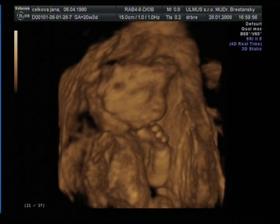

Nase prve male potesenie Martinko a ako rastie